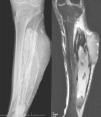

Clinical casesCase 1The first case was a 55-year-old male, with a history of a supracondylar femur fracture that was treated with osteosynthesis, 34 years before he was sent to our tumour unit. In the anamnesis, the patient referred to having presented repeated haematoma on the leg after the operation, which required successive debridement. As a result he was left with a lesion in the sciatic nerve that required a tendon transposition to correct the residual equinus. He later presented symptoms of swelling in the limb, which would clear up of their own accord, until nearly 4 years ago when he went to the hospital with a persistent tumour mass that did not disappear as previously: the diagnosis was of a synovial cyst. Due to the progressive growth of the tumour and increased pain, they performed a magnetic resonance imaging (MRI) that reported a soft tissue sarcoma, which was the reason he was sent to the tumour unit. On examination he presented good general health, with no toxic syndrome; what stood out was the presence of a soft tissue mass of about 20cm, which was hard, well defined and under tension, and took up the entire anterolateral compartment of the leg. The radiographic images showed a fusiform tumour with calcifications inside and with erosion at tibial cortical level (Fig. 1A). In the computerized tomography (CT), we could see a soft tissue mass in close contact with the anterior cortex and lateral cortex of the tibia, with multiple irregular central and peripheral calcifications (Fig. 1B). In the MRI (Fig. 1C), the lesion had hypointense areas that eroded the tibial cortical bone by disrupting it. We could see images suggestive of calcifications and irregular and hypointense margins, which indicated haemosiderin secondary to intralesional haemorrhage. Despite the fact that the clinical history and additional tests did not suggest a sarcoma, we carried out a biopsy that eliminated the presence of tumour cells. Later extensive debridement of the soft tissue mass revealed a coffee-coloured liquid, multiple elongated calcifications, degenerate mucoid tissue with muscle necrosis and remains of organized haematoma. We were able to extract nearly all of the mass and the cultures taken were negative. The histopathological study showed muscular necrosis and calcified bone matter, which suggested a diagnosis of calcific myonecrosis. The evolution was satisfactory, with correct healing of the wound, and the patient improved clinically. Seven years later there was no evidence of a recurrence.

(A) AP and profile X-rays of the left leg showing a large soft tissue lesion with irregular linear calcifications. (B) Consecutive CT slices with contrast showing the anterior position of the soft tissue mass, with linear, central irregular and irregular calcifications, of complex cystic content. We can also see the ossification of the interosseous membrane. (C) MRI axial T1-weighted sequences (right) and T2 (left), which show that the soft tissue mass has a heterogeneous appearance, corresponding to a complex liquid collection, while the calcifications have a very low signal in both sequences.